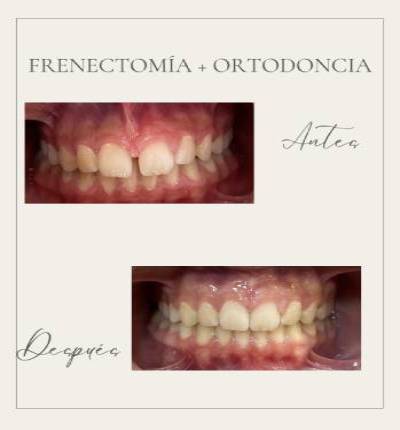

Ortodoncia y Odontopediatría

Ofrecemos tanto ortodoncia invisible con alineadores como ortodoncia fija con brackets.

Evaluamos cada caso y te recomendamos el más adecuado para ti. También ortodoncia para los más pequeños y los pacientes en crecimiento.

Extracciones dentales, incluyendo cordales y dientes retenidos.

Tratamientos realizados en nuestra clínica